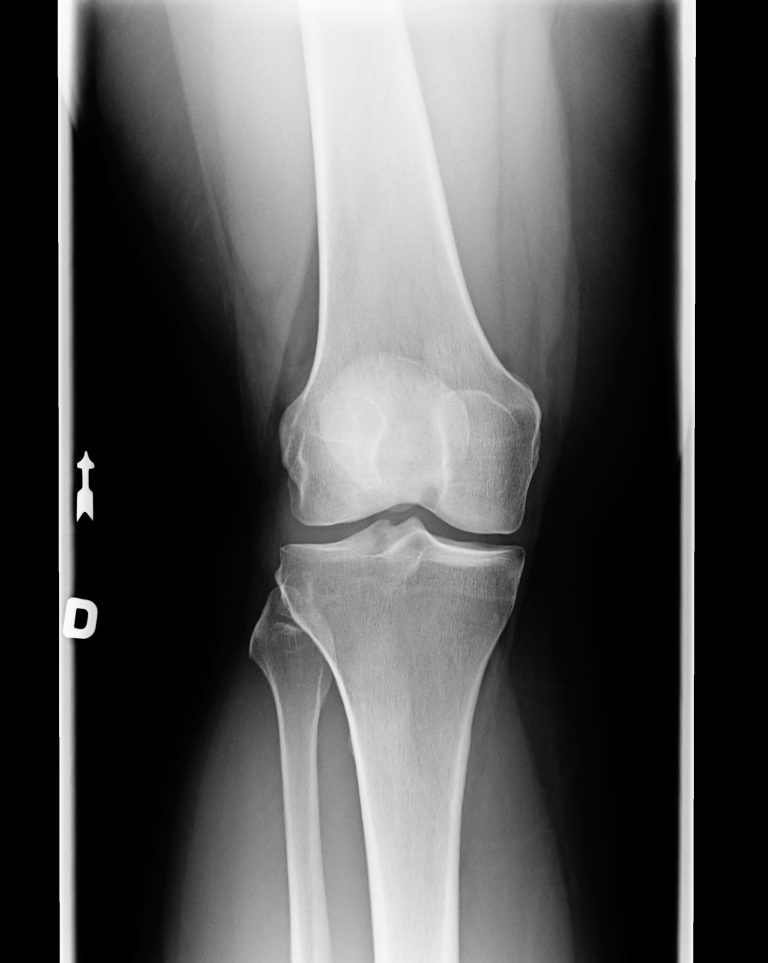

A precise survey of the pain symptoms, as well as a thorough clinical examination, can provide initial indications of possible cartilage damage in the knee joint. An X-ray examination of the affected knee is mainly used to exclude a bony injury, but may already indicate advanced cartilage damage or arthrosis if there are radiological signs of wear.

The diagnosis of cartilage damage is confirmed by magnetic resonance imaging (MRI), which can be used to determine the size and depth as well as the exact location of the cartilage damage. In addition, an X-ray examination of the leg axis should be performed if a malposition (knock knees or bow legs) is suspected, as this can often be the cause of the cartilage damage. In the case of cartilage damage to the kneecap, instability of the kneecap should also be investigated.